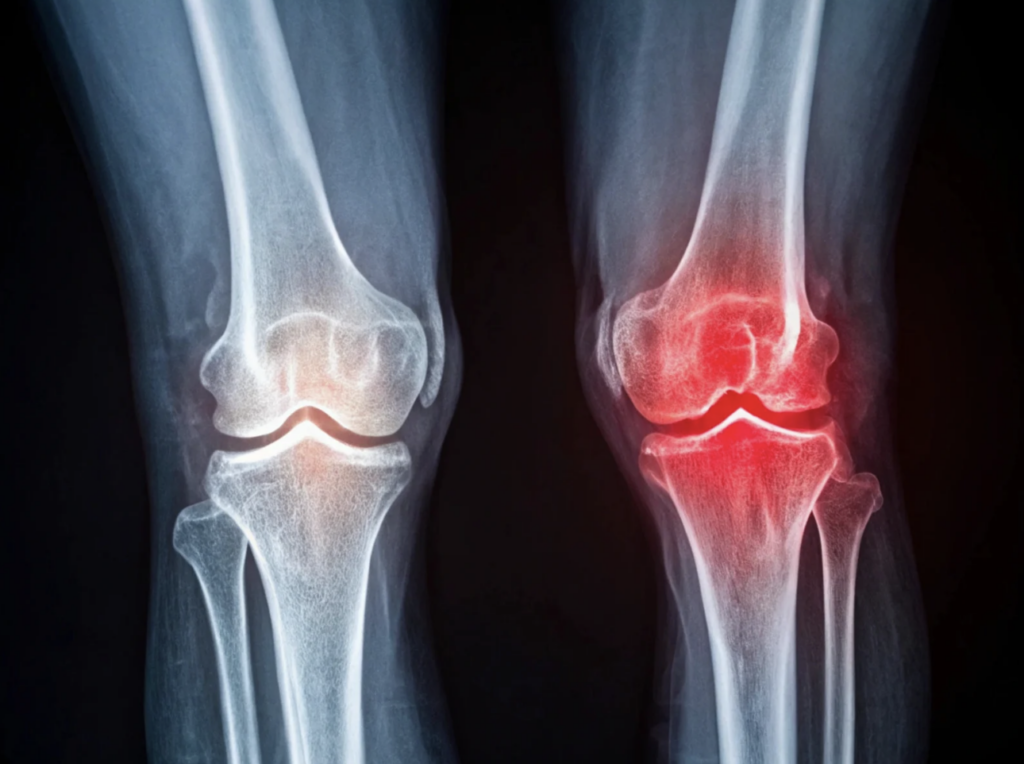

変形性膝関節症は、膝関節の軟骨が徐々にすり減り、骨同士が直接こすれることで痛みや変形が生じる疾患です。日本国内の潜在的な患者数は約3,000万人と推定されており、特に女性に多く見られます。70歳代では約70%、80歳代では約80%の方が膝の痛みで悩んでいるとされています。

軟骨破壊の抑制・再生が期待できる

変形性膝関節症では軟骨が徐々にすり減り、ついには関節が変形してしまいます。その病態に対しては、これまで有効な治療法がありませんでした。しかし培養幹細胞治療は、軟骨の保護や状態の維持が期待できます。病気の進行スピードを遅らせる効果も望めるのです。

海外で行われた研究では、生理食塩水を注射した群では軟骨の欠損が悪化したのに対し、培養幹細胞を注射した群ではその悪化が認められませんでした。さらに、現時点では症例数が少なく明確な結論には至っていませんが、培養幹細胞の投与によって膝の軟骨が再生して厚くなったという事例も確認されています。